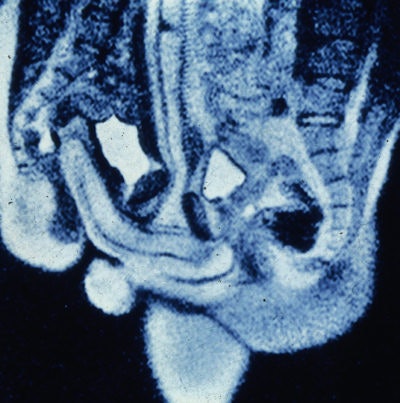

The determined researchers eventually concluded that MR images of coitus are both "feasible and beautiful." In addition, the shape of a man's penis, as seen on MRI, was not what previous research had suggested, and the size of a woman's uterus did not increase during sexual arousal.

The BMJ paper was hardly the medical equivalent of a moon landing, so why did visitors come flocking in such numbers? Delamothe suggested that the "prospect of seeing coitus on screen (for free) was the attraction, even if all that was on offer was a series of black and white still photographs."